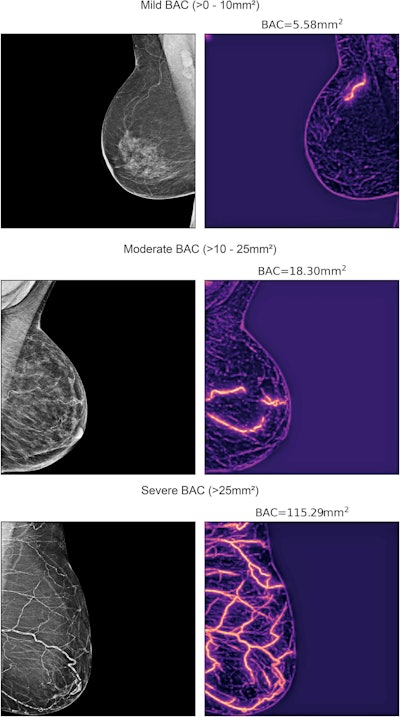

The retrospective cohort study included 123,762 women from two healthcare systems -- Emory Healthcare and Mayo Clinic Enterprise -- who had screening mammograms. The team used a transformer-based neural network for segmentation to calculate BAC severity by the following: zero (0 mm2), mild (>0–10 mm2), moderate (>10 mm2 to 25 mm2), and severe (>25 mm2).

Examples of mammograms with mild, moderate, and severe breast arterial calcification quantified by an AI model developed by researchers from Emory University and Mayo Clinic Enterprise. (Left) Original image. (Right) AI model heat map with breast arterial calcification score shown above.Images republished under a Creative Commons license (CC-BY-NC).